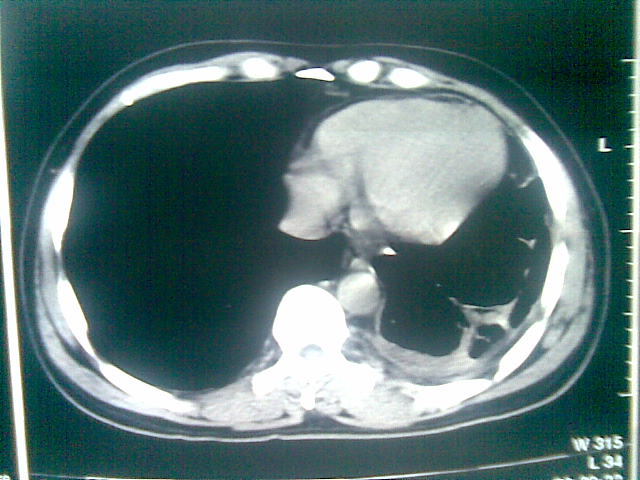

标题: CT23981:男,38岁阑尾炎术后透视胸腔积夜!做CT如下!积液包 [打印本页]

标题: CT23981:男,38岁阑尾炎术后透视胸腔积夜!做CT如下!积液包

可能与阑尾术后关系不太大,1.胸膜增厚粘连见少量气体。包裹脓气胸?左侧网膜囊脓肿?

.胸膜增厚粘连见少量气体。包裹脓气胸

左侧胸膜增厚、粘连+包裹液气胸。